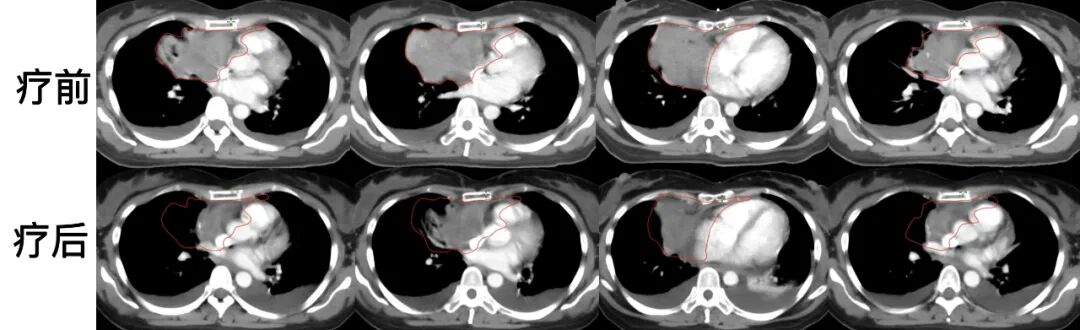

劉女士,48歲,活動后氣促,癥狀持續(xù)月余,逐步加重。胸部CT檢查顯示右肺中葉及縱隔巨大軟組織腫塊;胸腔積液;心包大量積液。患者入院后經(jīng)過腫物活檢:診斷為胸腺瘤,B2型。結(jié)合患者病情、病理及影像檢查,患者診斷為:胸腺瘤(B2型,Masaoka分期 IV A期),侵犯心包、胸膜。B2型胸腺瘤為具有局部侵襲性的腫瘤類型,胸腔和縱膈內(nèi)廣泛侵犯,無法直接進行手術(shù)治療。

圖注:CT檢查可見,腫瘤范圍巨大,緊臨心臟等重要器官;嚴(yán)重壓迫氣管,影響患者的呼吸。

患者放射治療過程順利,療后復(fù)查CT顯示,腫瘤病灶明顯縮退?;颊邭獯侔Y狀緩解,治療結(jié)束后順利出院。療后胸水及心包積液引流量逐漸減少,治療后2個月完全消失。

圖注:放療前后腫瘤區(qū)域CT對比,上排為放療前,可見胸腔及縱膈內(nèi)腫瘤巨大,造成心包及縱膈受侵。下排圖像治療后,腫瘤病灶明顯縮小。